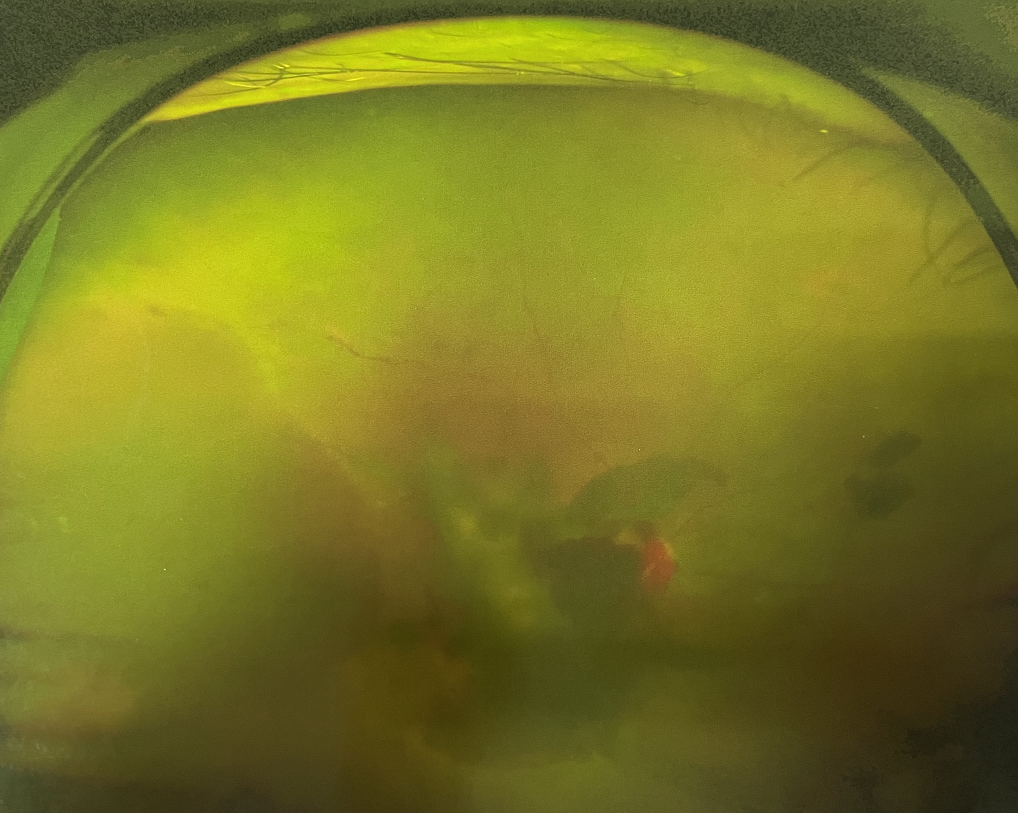

糖尿病視網(wǎng)膜病變是糖尿病在眼部的主要并發(fā)癥,是我國四大致盲眼病之一,主要以視網(wǎng)膜血管改變?yōu)椴±硖卣?。眼底多表現(xiàn)為視網(wǎng)膜出血、滲出、新生血管及增殖膜形成,嚴(yán)重威脅患者的視覺健康。

糖尿病視網(wǎng)膜病變可分為六期:

?、衿冢河形⒀芰龌虿⒂行〕鲅c(diǎn)。

?、蚱冢河悬S白色“硬性滲出”或并有出血斑。

?、笃冢河邪咨?ldquo;軟性滲出”或并有出血斑。

?、羝冢貉鄣子行律芑虿⒂胁Aw積血。

Ⅴ期:眼底有新生血管或并有纖維膜增生。

Ⅵ期:眼底有新生血管或并有纖維膜增生,并發(fā)視網(wǎng)膜脫離。